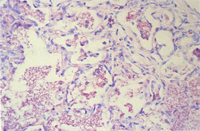

肉眼病變: 肺臟堅實,不規則斑駁狀棕灰色肝變區域(圖1)。

組織病變: 許多肺泡可見顆粒狀、泡沫狀、嗜酸性之無組織結構物質不規則散佈於肺泡中,間 雜肺泡巨噬細胞,少量嗜中性球,圍小支氣管及圍血管淋巴球及漿細胞增生,肺泡第二 型細胞增生(圖2,3)。